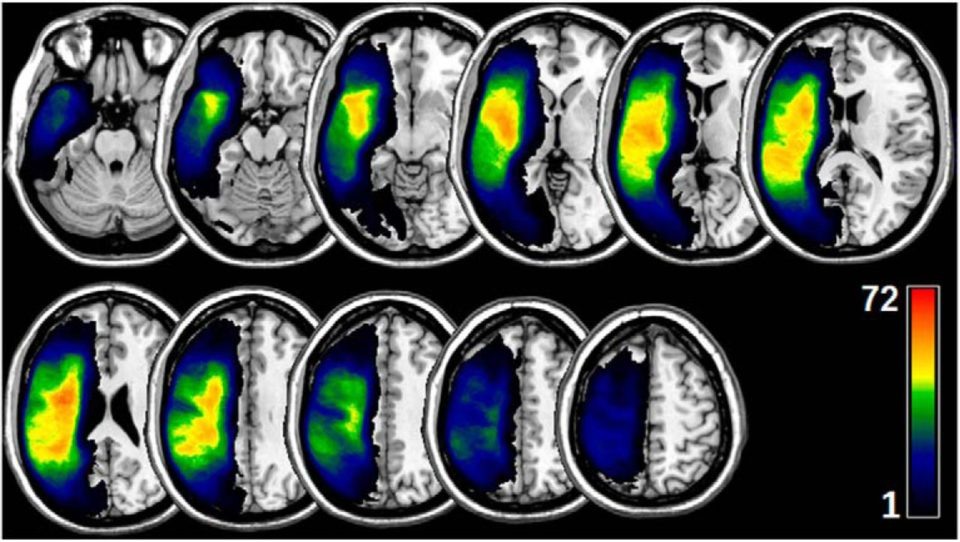

Зоны серого вещества (слева) и связи в белом (справа), важные для сохранения речевых функций. Сверху — предсказание восстановления для функций повторения речи, внизу — для функции называния предметов. Иллюстрация Dr. Leonardo Bonilha and Dr. Grigori Yourganov of the Medical University of South Carolina.

Опубликованная в Journals of Neuroscience работа американцев, проведенная под руководством докторов Григория Юрганова и Леонардо Бониха доказывает, что для лучшего прогноза постинсультной реабилитации нужно изучать не только поражения серого вещества (коры полушарий), но и белого, связывающего зоны мозга друг с другом. Это — первая работа, посвященная томографическому изучению коннектома постинсультных пациентов и влиянию поражения аксонов на языковые функции.

Кроме этого, исследование помогло понять и роль некоторых зон мозга в речи. Так, например, впервые было установлено, что соединения в теменной области очень важны для функции языка, особенно его беглости. Любопытно, что теменная область чаще других страдает при инсульте, а нарушения коннектома не видны на обыкновенном структурном МРТ, поэтому обычными методами сложно предсказать поражения речи.